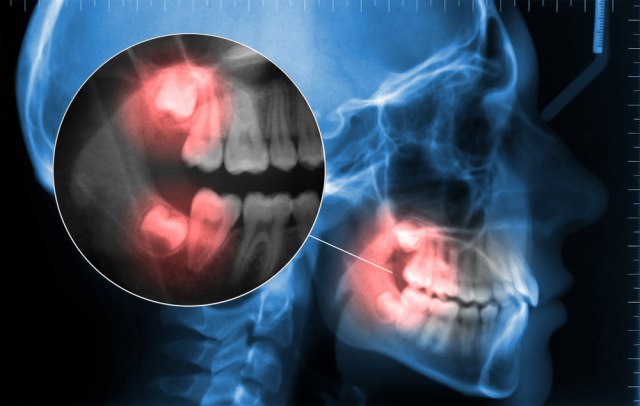

Misterija izbijanja kutnjaka, koji najčešće krenu da rastu krajem tinejdžerskih godina, već neko vreme muči naučnike. Ali stručnjaci sa Univerziteta Arizona u SAD-u smatraju da su shvatili o čemu se radi.